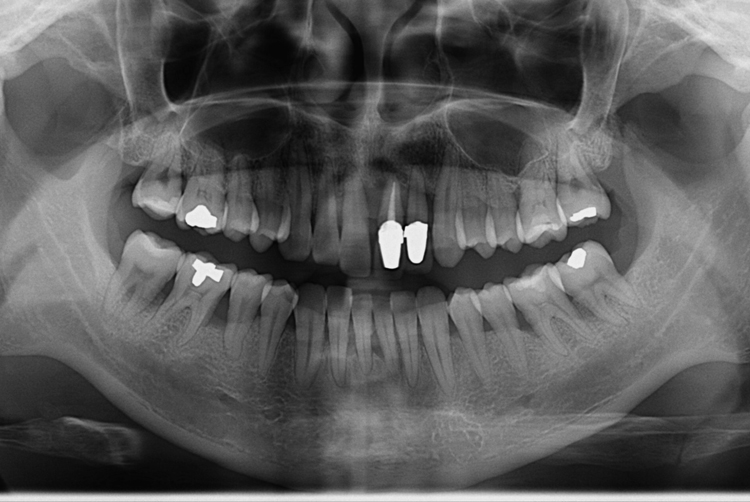

[임플란트] 앞니 임플란트

치료전 : 2019-09-18

세종치과는 많은 환자와 다양한 케이스를 바탕으로

항상 편안한 임플란트 수술을 제공하고자 노력하고,

오래동안 튼튼히 쓸 수 있는 임플란트 수술을 가장 큰 목표로 삼고 있습니다.